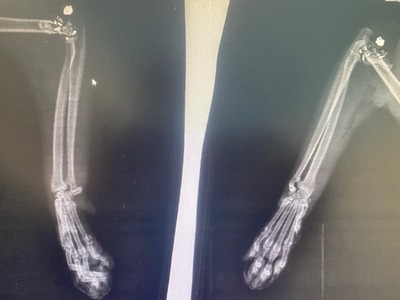

Στο μεταξύ σύμφωνα με την καταγγελία που έφτασε στο thebest.gr, γάτα στην ίδια περιοχή, στο Σκαγιοπούλειο, δέχτηκε πυροβολισμό ωστόσο ευτυχώς δεν τραυματίστηκε θανάσιμα.

Η ακτινογραφία της γάτας που δέχτηκε πυροβολισμό όπως καταγγέλλεται